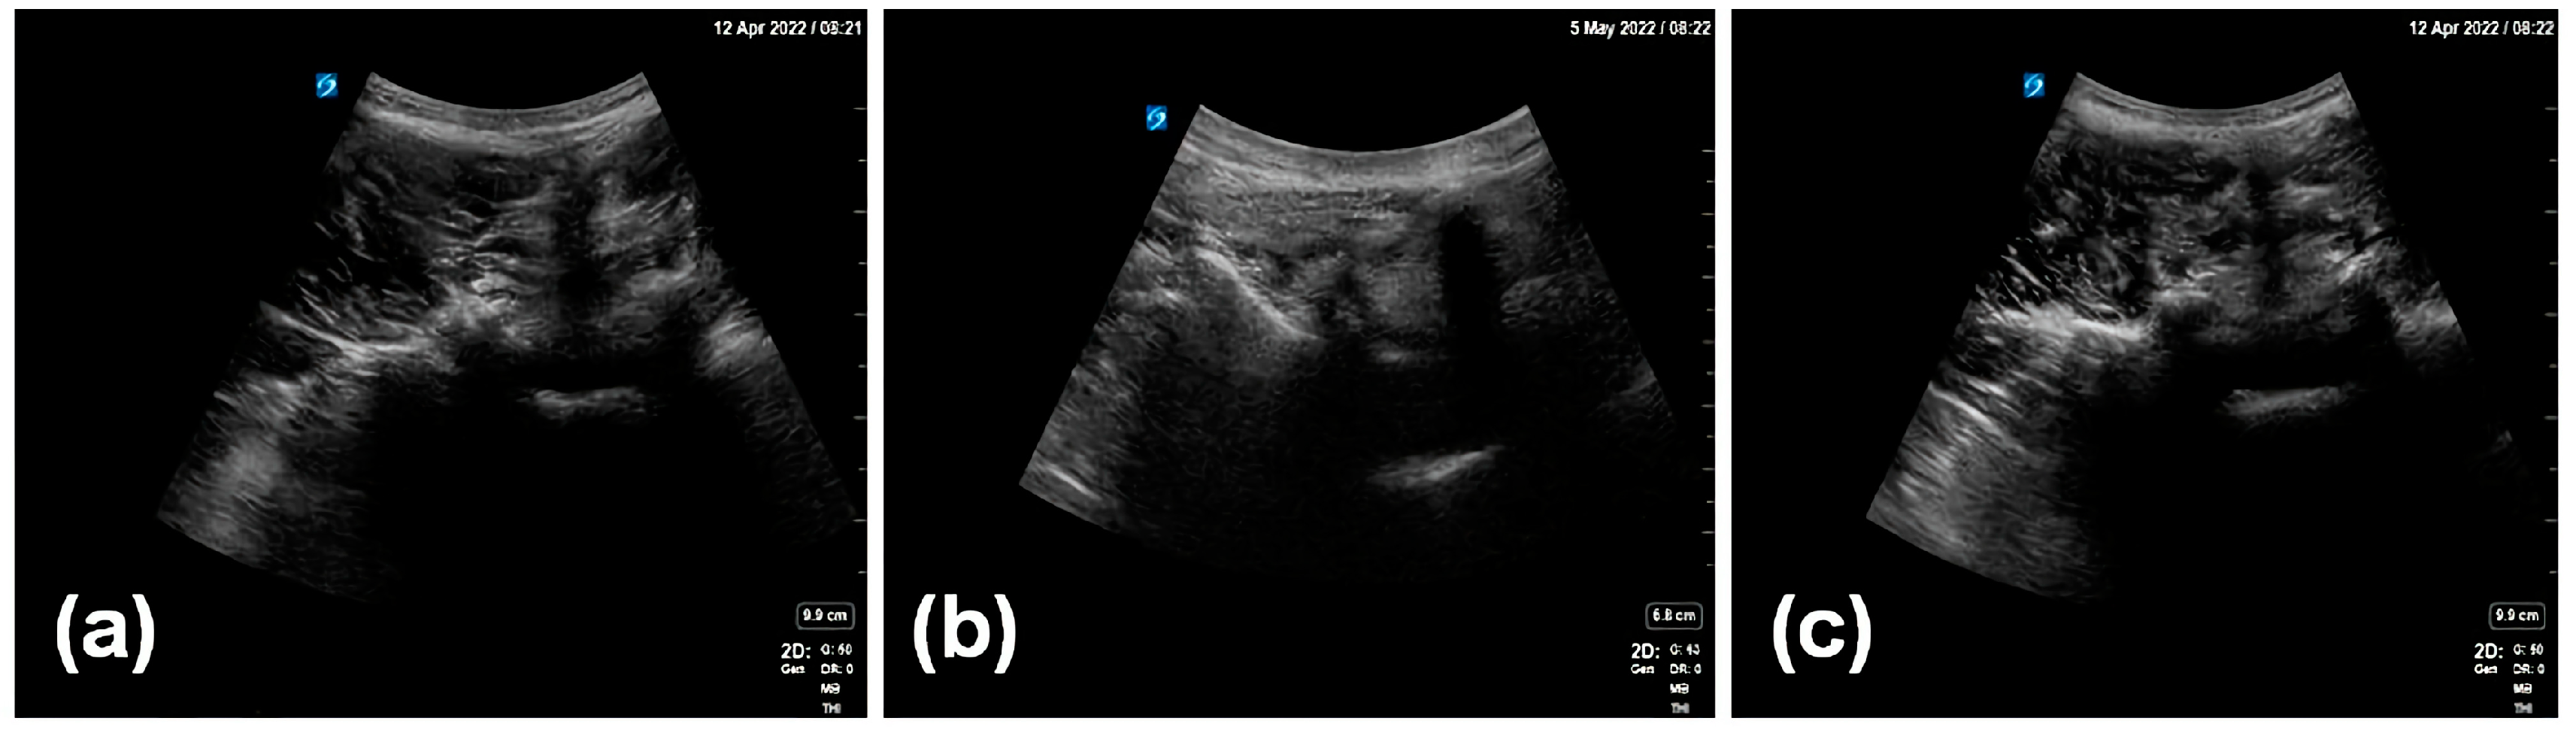

The considerations of the enhanced data annotation method proposed in this work are discussed. The ventral complex can assist in the detection and recognition of the facet joint. For instance, if there are facet joint–transverse process objects appearing in ultrasound images, with no dura mater appearing, then the facet joint–transverse process object detection may be true, or false. However, if there are facet joint–transverse process objects appearing in ultrasound images, with dura mater appearing, then facet joint–transverse process object detection should be true. The dura mater is the structure inside the spinal canal. If the dura mater appears in the ultrasound image, it means that the ultrasonic scanning plane must be at the level of the intervertebral space, and the facet joint–transverse process is also at the level of the intervertebral space. Therefore, the facet joint–transverse process must be true at the level where the dura mater can appear. However, if the facet joint–transverse process appears in the absence of dura mater, it may be that the ossification and calcification of intervertebral tissue has caused a failure to recognize the dura mater in ultrasound images, or it may be due to other tissues whose structures are similar to the facet joint–transverse process. With the enhanced data annotation method and combined identification of the facet joint and ventral complex, the negative sets can be correctly recognized (Figure 6).

Figure 6. Detection of a negative set using the proposed method.